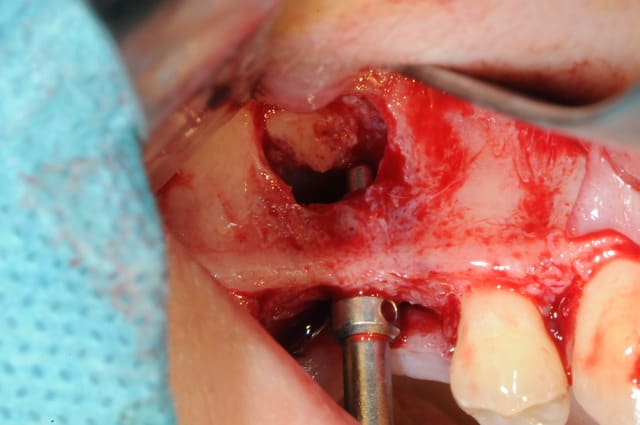

le sujet tombe à pic!

je viens de faire un sinus lift ce matin;

- 3 à 4 mm de hauteur sous sinusienne

- des cloisons de refend partout

- comblement avec du Vital Os

- un implant Axiom D4 L 10

comme je n'avais pas le temps de faire des photos la dernière fois et que j'en étais frustré, je me suis un peu lâcher aujourd'hui...

les premières photos, c'était ouverture par voie latérale